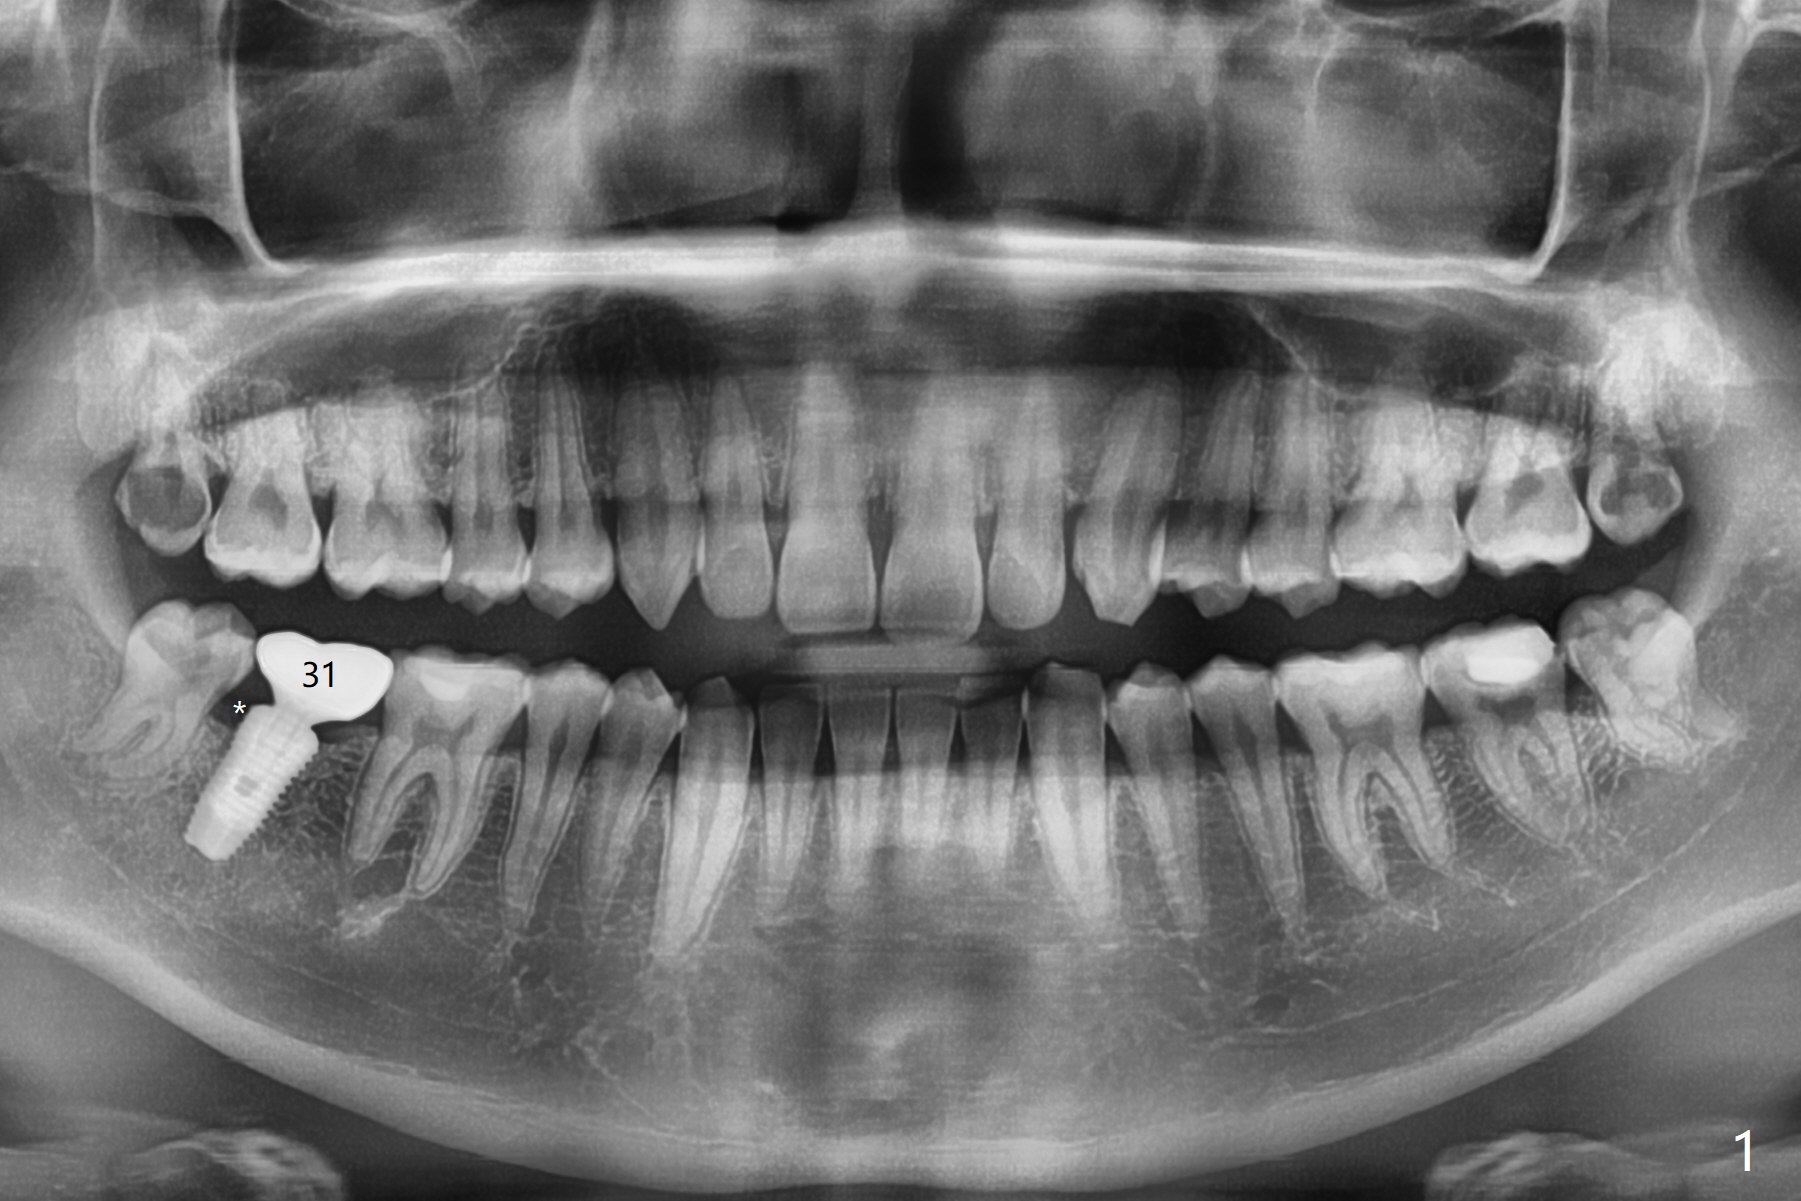

A 26-year-old man returns for #17,32 extraction 5.5 months post #1,16 one (Fig.1,2). In fact the crown/abutment at #31 is loose and removed, which makes easy for access, debridement with Titanium brush and bone graft (Fig.2 arrowheads, Ossogen). Osteogen plug is placed in the extraction sockets. The patient has limited mouth opening. Hemorrhage in #17 socket is controlled apparently with the plug following incomplete removal of granulation tissue. A piece of 12x12 mm Amnion-Chorion Membrane seems small for bone graft coverage. Cytoplast is added, followed by PGA suture. The former may keep the bone graft in place in case the wound dehisces. In fact the implant was not placed deep enough. It should have been removed. Although the wounds at #31/32 and 17 heal 7 days postop (Fig.3,5), the Cytoplast is visible immediately underneath the lingual gingiva at #31 (Fig.4 * (bulging)). The patient returns for Cytoplast (Fig.6 (occlusal view) *) removal 5 weeks postop. The procedure is done smoothly.